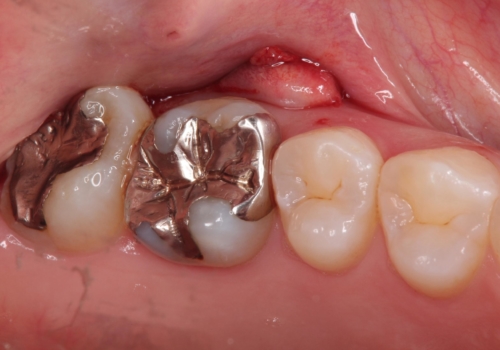

根の神経の治療を行い、セラミックを装着する計画としました。

根の神経が細菌に感染するとこのように、膿の出口ができることがあります。

その場合は、根の中の治療(根管治療)が必要になります。